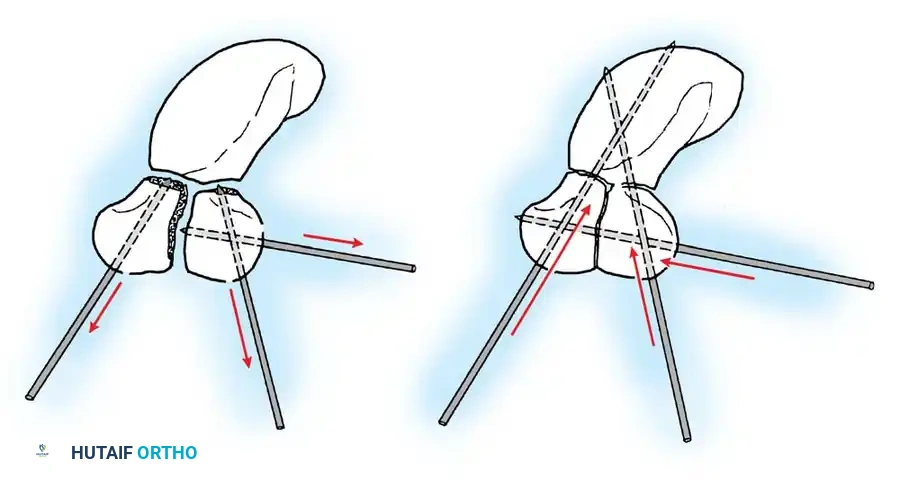

Closed reduction with percutaneous pinning (placing 0.045-inch K-wires from the scaphoid to the capitate and lunate) can be attempted. However, open reduction through a dorsal approach is generally preferred. This allows direct closure of the scapholunate gap, K-wire fixation, and primary repair of the dorsal SL interosseous ligament using suture anchors.